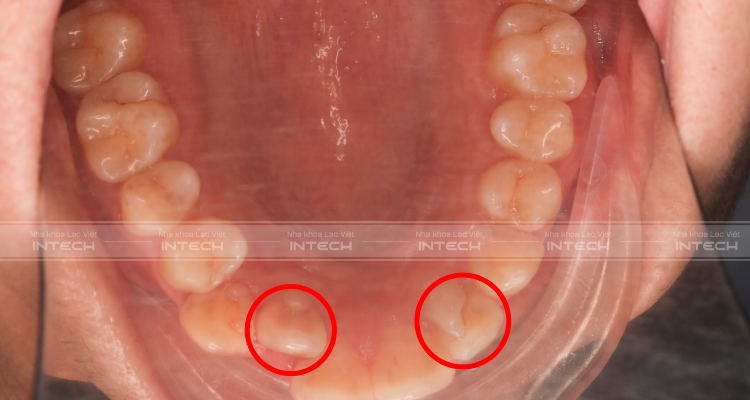

- Chen chúc khấp khểnh cả hai hàm ở mức độ trung bình

- Răng cửa hàm trên bên trái bị mọc kẹt vào trong làm cho toàn bộ hàm trên bên trái bị xô sang bên phải khiến đường giữa hàm trên và hàm dưới bị lệch

Phần hàm trên bên trái có răng cửa có hình thể bất thường.

Đường giữa hai hàm răng lệch

Răng cửa hàm trên mọc kẹt